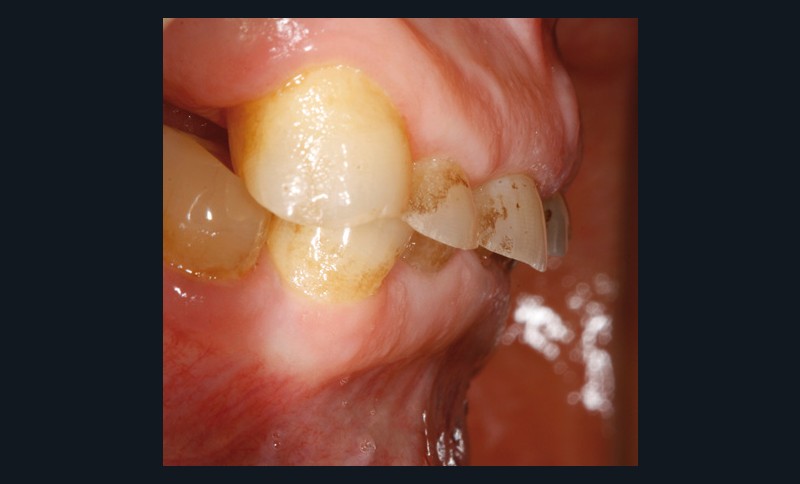

• L’examen intrabuccal montre de nombreux édentements non compensés (14, 15, 16, 24, 25, 26, 27, 47 et 36) ainsi que des pertes de substance très importantes, notamment dans le secteur antérieur.

Une attrition sévère, couplée à une occlusion sans calage postérieur, a engendré des difficultés pour s’alimenter.

– perte de substance extrême du bloc incisivo-canin maxillaire et des incisives mandibulaires ;